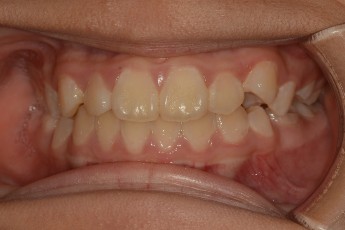

BEFORE & AFTER

- 덧니교정